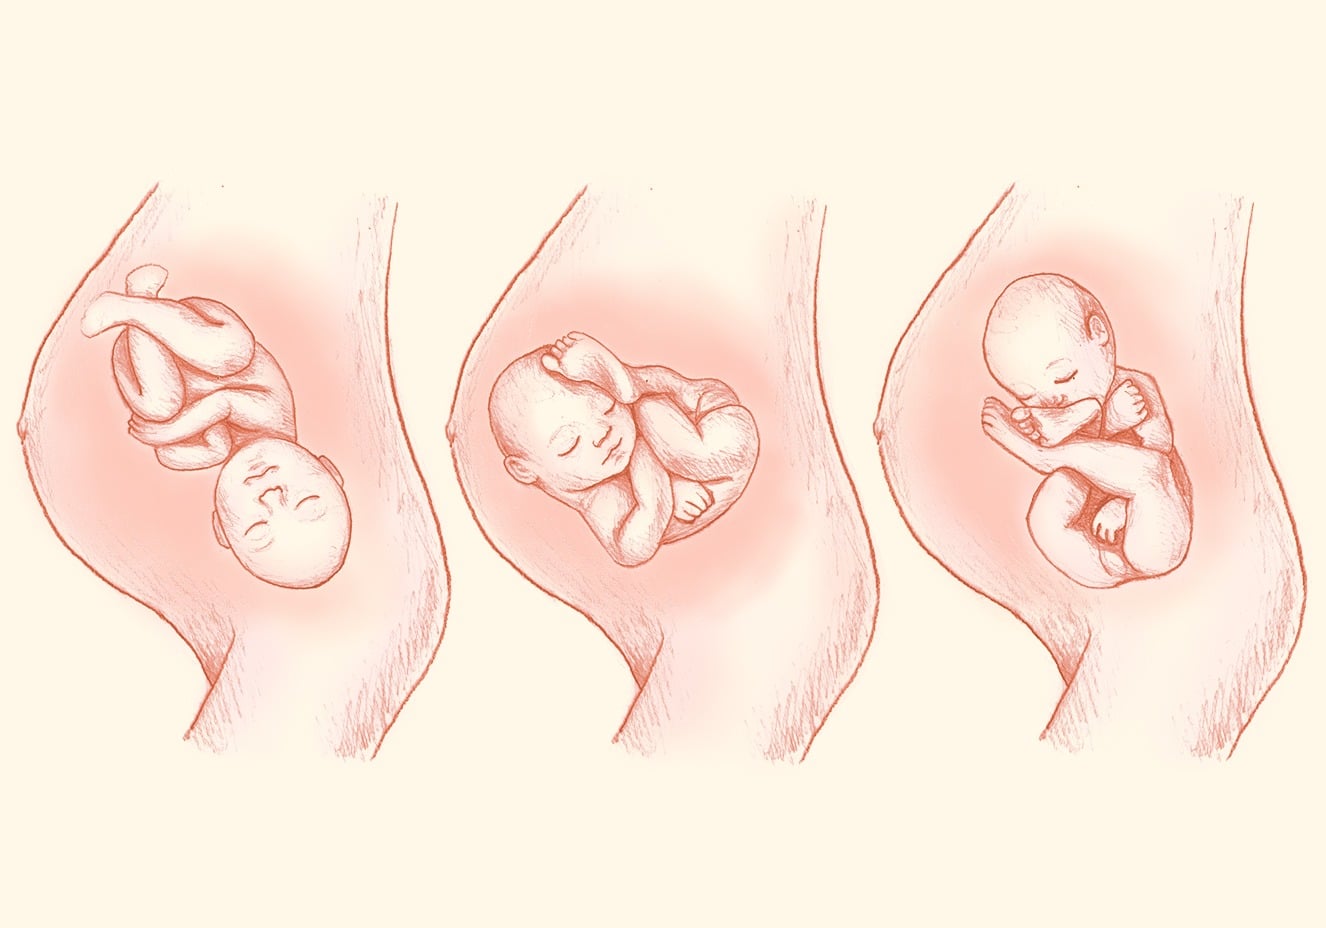

Во время беременности, положение плода имеет большое значение для мамы и малыша. Одним из типичных положений является продольное предлежание головное. В этом положении голова малыша находится внизу, а ножки - наверху. Это положение достаточно распространено и предпочтительно для естественных родов.

Фото положения плода во время беременности

Ниже приведены несколько фотографий, которые помогут вам визуализировать положение плода во время беременности.